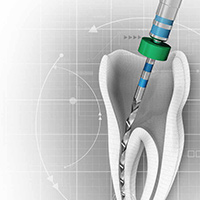

New Directions in Endodontics

Tuesday, April 2, 2024

This Compendium eBook features a continuing education (CE) article on the management of endodontic flare-ups. This eBook also includes an article on intentional replantation as a predictable and cost-effective option for preserving a natural tooth and as a favorable alternative to conventio...

One-Day Endo-Restorative Treatment: The Integration of Advanced Technology and a Single-Visit Workflow for General Dental Practitioners

Scott Sayre, DDS, MBA, MAS

Monday, February 26, 2024

This Compendium eBook offers a continuing education (CE) article that explores the integration of technology as part of a single-visit workflow for root canal therapy that can be implemented by the general dentist. Download to earn 2 complimentary CEU now!

Endodontic Pathways

Friday, September 29, 2023

This Compendium eBook features a continuing education (CE) article on the prevention and management of endodontic rotary nick-titanium (NiTi) file breakage. An article describing advances in endodontic care and pain management is also included in this eBook. Download to earn 2 complimentary...

Endodontic Updates

Wednesday, March 22, 2023

This Compendium eBook offers a continuing education (CE) article on unseparated fractures and their diagnostic complexities. This eBook also includes a case report article on the use of cone-beam computed tomography for the analysis of atypical root canal anatomy. Download to earn 2 FREE CE...

Endodontic Advances

Friday, October 21, 2022

This Compendium eBook offers a continuing education (CE) article that examines the most recent guidelines of the American Association of Endodontists and the American Dental Association regarding the prescription of antibiotics, and outlines the best choices for antibiotic treatment for bot...

Endodontic Solutions

Friday, April 1, 2022

This Compendium eBook offers a continuing education (CE) article that reviews the application of selective anesthesia and presents cases in which these techniques were used to facilitate the accurate diagnosis of endodontic disease.This eBook also includes an endodontic case report focusing...

Breakthroughs in Endodontics

Monday, October 4, 2021

This Compendium eBook offers a continuing education (CE) article on the critical decision-making process involved in determining whether to restore or replace compromised maxillary anterior teeth, with an emphasis on the importance of timely treatment decisions and their criteria. In addit...

Developments in Endodontics

Wednesday, July 14, 2021

This Compendium eBook offers a continuing education (CE) article on mineral trioxide aggregate (MTA) and its composition, clinical applications, and research findings. This eBook also includes a case report on the use of conebeam computed tomography (CBCT) to diagnose anatomical disparities...

Advancements in Endodontics

Monday, August 31, 2020

This Compendium eBook consists of a continuing education (CE) article on ridge preservation strategies in children who experience anterior tooth trauma. A second article is a case report that uses cone-beam computed tomography (CBCT) for diagnosis, evaluation, and endodontic management of a...

Innovations in Endodontics

Friday, May 8, 2020

This Compendium eBook offers a continuing education (CE) article that features the importance of proper pretreatment diagnosis and the identification of etiology in endodontic retreatment. A second article provides an up-to-date report on comprehensive endodontic pain management.

Innovative Technologies Within Endodontic Practices to Improve Treatment Outcomes: The Importance of Patient Referral

Wednesday, November 20, 2019

This Compendium eBook features a continuing education (CE) article on advancements in technology that have provided a better understanding of the complex anatomies found in root canal systems.

Spotlight on Endodontics

Thursday, August 1, 2019

This Compendium eBook includes a CE article that describes techniques for placement of posts. The second article presents a case report on a multidisciplinary approach to the management of a mandibular first molar.

Today's Trends in Endodontics

Wednesday, February 6, 2019

The relationship between endodontics and restoration is explored in two continuing education (CE) articles presented in this special Compendium eBook. The first article explains the importance of obtaining a pulpal and periradicular diagnosis before restorative treatment. The second discuss...

Current Topics in Endodontics

Monday, September 24, 2018

This special Compendium eBook presents two articles on topics in endodontics. The first article, a continuing education course with a quiz for 2 credits, examines various steps of endodontic treatment and how, from a restorative standpoint, treatment can be improved for better long-term predictabili...

Advances in Endodontics

Wednesday, February 14, 2018

This eBook provides two continuing education articles on endodontics topics. The first article reviews solutions to the problem of endodontic rotary file breakage. In the second article, the authors examine mineral trioxide aggregate (MTA), a material that has become vital in endodontic dentistry.

Updates in Endodontics

Wednesday, December 6, 2017

This special Compendium eBook provides two CE articles to increase practitioners' knowledge of endodontics topics. The first article describes the vital role that irrigation plays in successful endodontic treatment. The second article addresses the complexity of the pulp root canal and the difficult...

Endodontics

Monday, April 17, 2017

This special Compendium eBook discusses how local anesthesia can be used to provide pain-free endodontic therapy. Also, a successful pulp capping procedure is described along with stepwise excavation associated with restorative treatment for deep caries lesions. Download today and earn 4 FREE CEU!

Clinical eBook Series: Endodontics

Thursday, April 21, 2016

With more than 24 million endodontic procedures being performed in the United States annually, endodontists are discovering new methods and technologies to treat their patients effectively, quickly, and comfortably. This eBook examines topics aimed at helping endodontists master their craft.